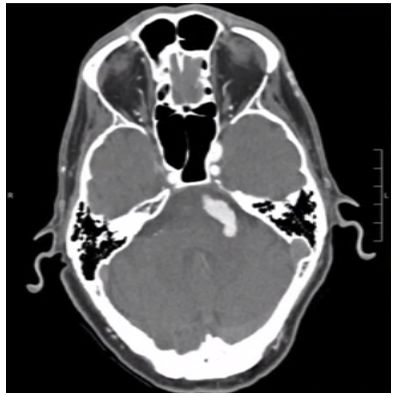

58岁男性患者,临床表现为左侧面肌痉挛,术前影像学检查诊断为基底动脉扩张延长症,导致左侧面神经受压(图1)。经患者同意后进行手术。手术采用远外侧入路,通过扩大枕下乙状窦后切口,显露基底动脉。基底动脉在中脑-脑桥连接处水平压迫左面神经根部。用muslin棉条制成悬带套住基底动脉,在斜坡硬脑膜上用19号针穿刺一孔;取一枚7mm直动脉瘤夹,将悬带末端栓系于动脉瘤夹一端,再将动脉瘤夹另一端穿入硬脑膜上破孔,把悬带锚定于硬脑膜上。通过拖曳悬带调整基底动脉的张力,最终将基底动脉从面神经上完全移开后,固定之(图2)。术后复查的CT及CTA显示,面神经不再受扩张、延长的基底动脉压迫(图3)。值得注意的是,由于手术野狭窄,在进行悬带套过基底动脉和移位的过程中,应避免过度牵拉致使穿支血管撕裂,一旦出血可能导致极其严重的后果。

图3. 术后CT和CTA。